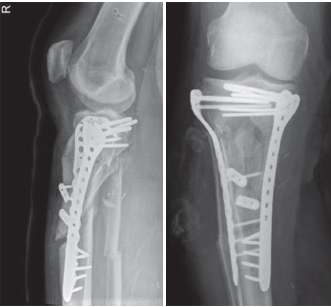

Three months following the injury it was determined that the diaphyseal component had no significant union or callus. The patient underwent removal of all of the infected metal. Extensive purulence was noted in the medullary cavity throughout the metaphysis. The non-union sites were aggressively debrided to bleeding healthy bone (Figure 6). The tibial canal was then reamed to prepare for a tibial nail using an infrapatellar approach so as to avoid inoculating the knee joint with infected debris. An injectable antibiotic loaded bio-composite (Cerament V and G — containing vancomycin and gentamicin) were then inserted through the non-union sites into the canal followed by an intramedullary nail (Figure 7). A blocking screw was used to address the procurvatum deformity in the sagittal plane. A medial gastrocnemius flap and skin grafting was then performed by plastic surgeons. Samples from this surgery grew methiillin resistant Staphylococcus Aureus (MRSA), Pseudomonas Aeruginosa, Candida Parapsilosis, Enterococcus Faecium and Staphylococcus Haemolyticus. Of these samples the dominant growths were Pseudomonas (sensitive to Gentamincin), Candida (sensitive to fluconazole) and MRSA (sensitive to linezolid). Post-operative antimicrobial treatment included ceftazidime, linezolid, ciprofloxacin and fluconazole.

Figure 7. Plain X-rays after removal of dual plate fixation. Cerament V was inserted into canal and then intramedullary tibial nail was inserted

After a period of three months, the patient’s antibiotics have been discontinued, however he remains on Fluconazole for at least another 6 months. Despite these challenges, the patient currently shows signs of recovery, mobilizing over short distances, weight-bearing with assistive aids and with healing wounds and early signs of callus formation on recent CT scans and plain X-rays (Figure 8, 9, 10). His inflammatory markers have improved significantly with a latest C-reactive protein of 14.7 from 250 mg previously (reference range 0-5) and normal white cell and neutrophils count.

Figure 8. Plain X-rays 3 months after removal of dual plate fixation with insertion of cerement V and intramedullary nail showing satisfactory alignment and early callus formation